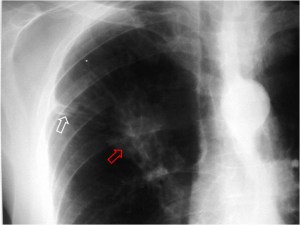

Imagen visible en la radiografía de tórax y en la TC que consiste en una banda radiodensa (flecha blanca) que desde un nódulo pulmonar (flecha roja) se extiende hasta la superficie pleural, en donde a menudo existe un engrosamiento focal. Este signo, descrito inicialmente como signo de malignidad, no es 100 % específico.

La imagen corresponde a un paciente con carcinoma epidermoide de pulmón.

Un ejemplo del signo (flecha blanca) en otro paciente, también con carcinoma de pulmón (flecha roja). Existe un derrame pleural derecho asociado.